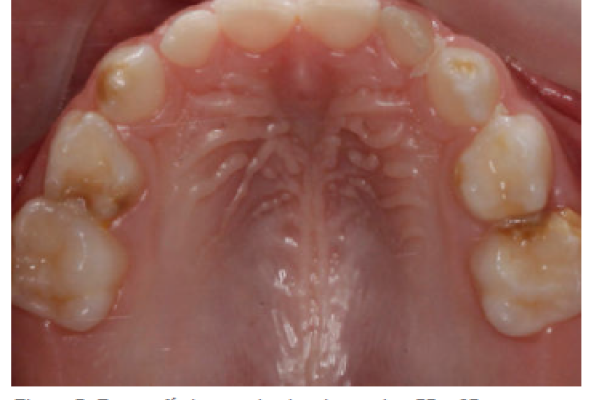

3 | FOTO CLÍNICA | HIPOMINERALIZACIÓN EN DENTICIÓN TEMPORAL: ¿FACTOR PREDICTIVO DE HIM? VELAYOS GALÁN, L. PIÑEIRO HERNÁIZ, M. ARNER CORTINA, C. ESPÍ MAYOR, M. ADANERO VELASCO, A. |

Hipomineralización en dentición temporal: ¿factor predictivo de him?